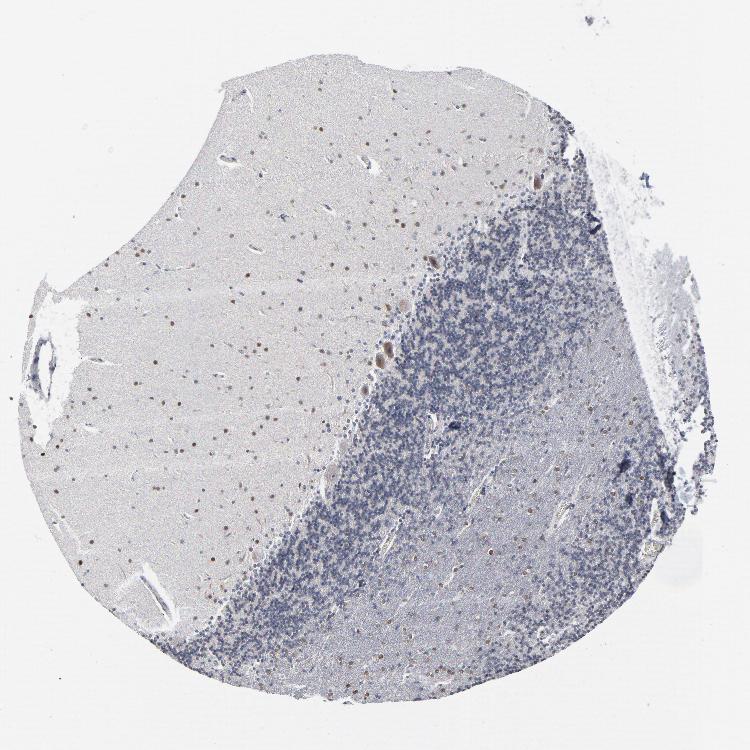

BRAIN CEREBELLUM Show tissue menu

CEREBELLUM - Antibody stainingi

Antibody staining in the annotated cell types in the current human tissue is reported as not detected, low, medium, or high, based on conventional immunohistochemistry profiling in selected tissues. This score is based on the combination of the staining intensity and fraction of stained cells.

Each image is clickable and will lead to virtual microscopy that enables deeper exploration of all samples and also displays staining intensity scores, fraction scores and subcellular localization as well as patient and tissue information for each sample.

Antibody HPA003485

Purkinje cells - cytoplasm/membrane Low

Purkinje cells - dendrites Low

Purkinje cells - nucleus Not detected

Granular cells - cytoplasm/membrane Not detected

Granular cells - nucleus Medium

Molecular layer cells - nucleus Medium

White matter cells - nucleus Medium